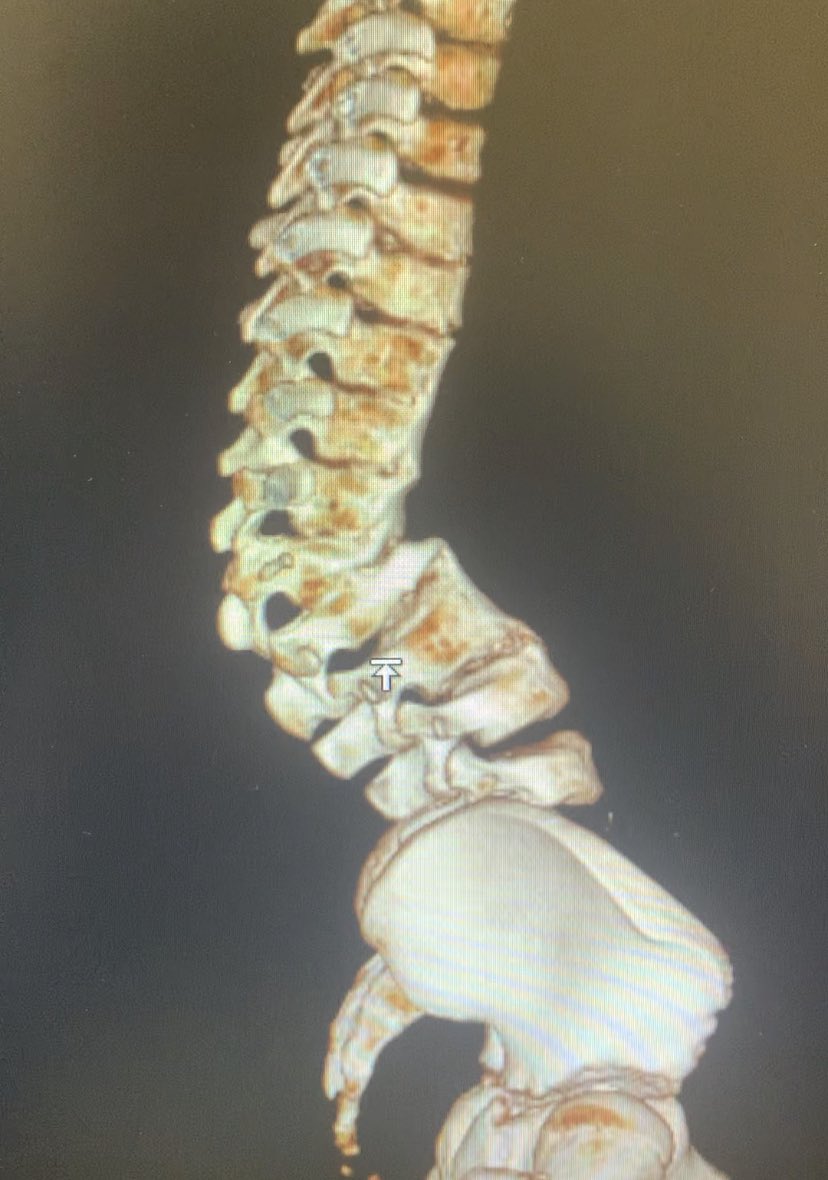

10 y o male, congenital kyphosis case. treatment with kyphectomy and double fibula allograft. #spinesurgery #spine